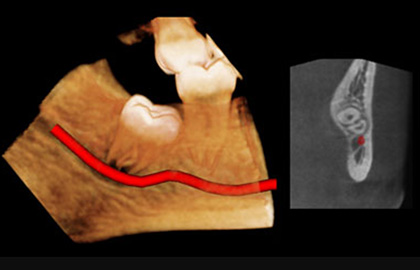

사랑니가 뼈속에 아주 깊이 박혀있는 경우 치아발치후 신경손상 등의 문제가 발생 할 가능성이 높습니다.

연세하루치과에서는 치과용 CT를 촬영으로 사랑니의 정확한 입체적 위치를 확인가능하기 때문에 안전하게 사랑니 발치를 시술 받으실 수 있습니다.